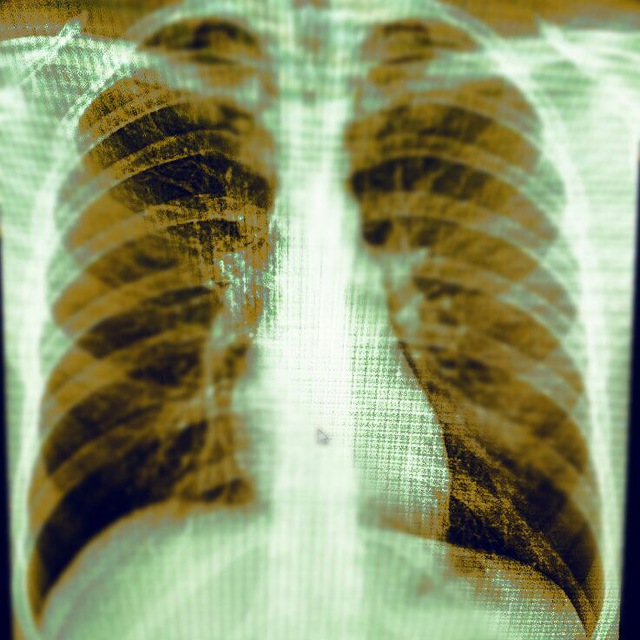

Здравствуйте! 39 лет. Т.37-39. Выраженная одышка.

Могу дать заключение репаративные изменения, стадия рековалесценций.?

Могу дать заключение репаративные изменения, стадия рековалесценций.?

Могу дать заключение репаративные изменения, стадия рековалесценций.?

Вы имели ввиду ретикулярные изменения и фиброз при эволюции вирусной пневмонии?

В принципе можно сочинить про перенесённый ковид и тд